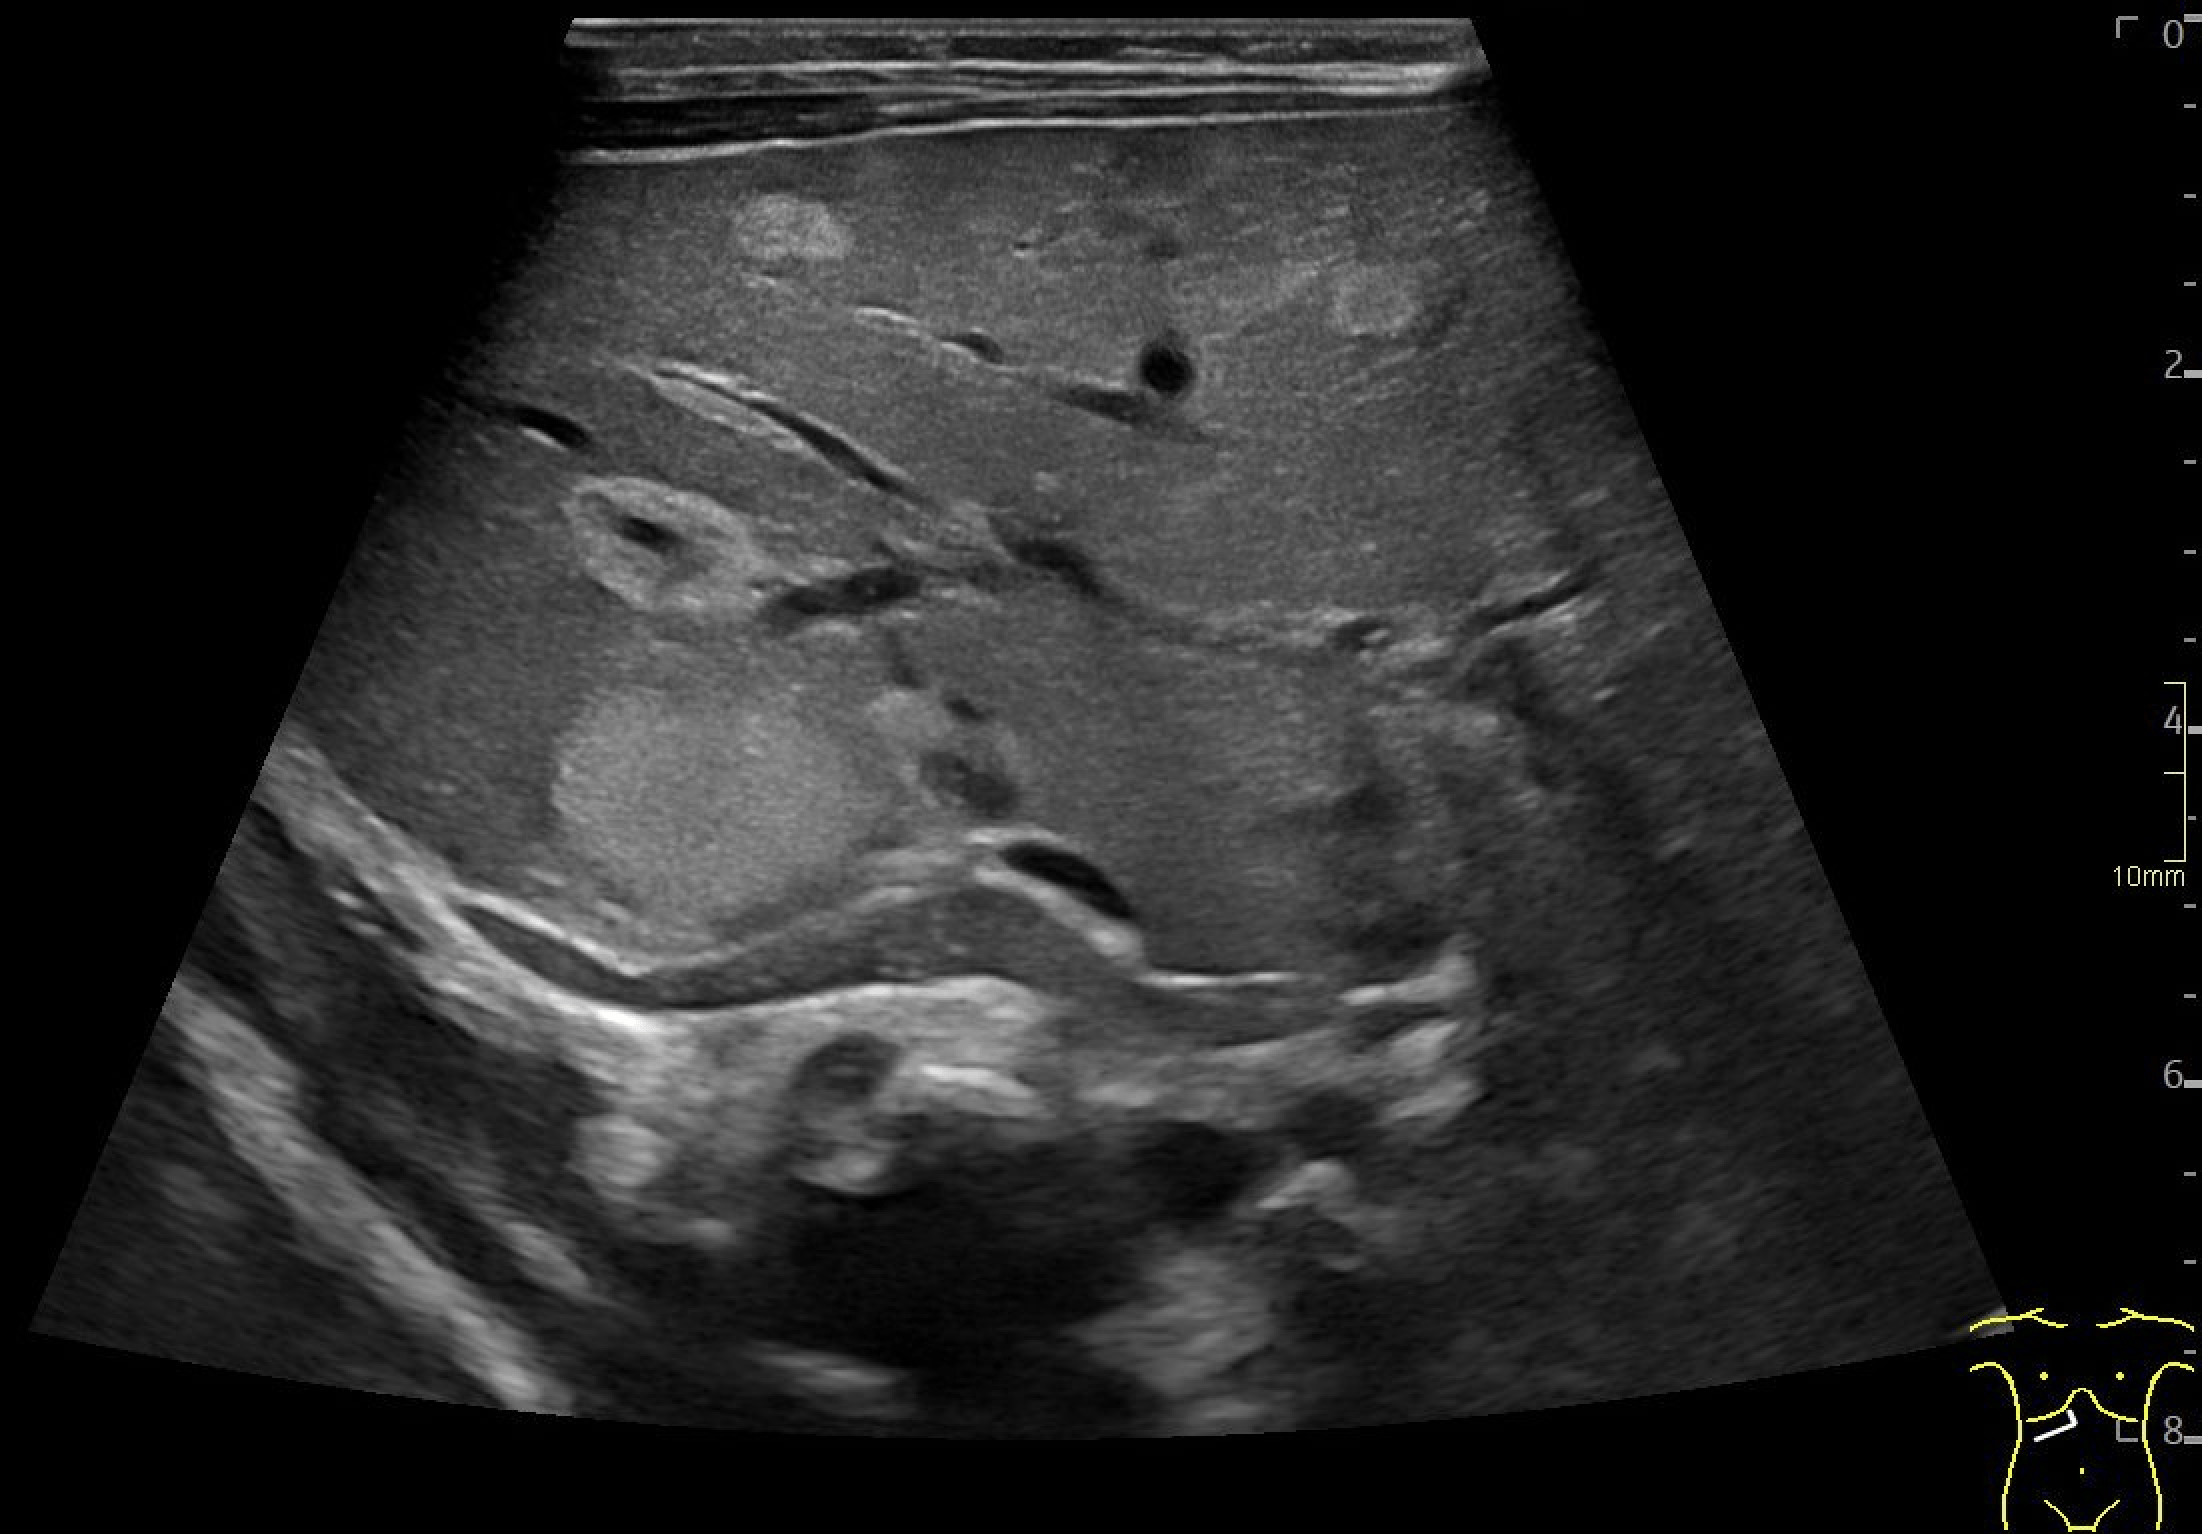

B: Doppler image of capillary hemangioma located ventrally in the right hepatic lobe, demonstrating large, tortuous vessels suggestive of possible arteriovenous shunting.

Multiple hepatic lesions were identified on ultrasound (A). Some lesions appeared as typical, well-defined hyperechoic cavernous hemangiomas (2), while others demonstrated large, tortuous vessels. Additional lesions showed a hyperechoic rim with a hypoechoic center and internal Doppler flow, consistent with capillary hemangiomas (2). In some HH (B), arteriovenous shunting was suspected. However, Triplex Doppler examination demonstrated normal hepatoportal flow in the portal vein (C) with flow velocities below 40 cm/s – within the normal range for the age – as well as a normal triphasic flow pattern in the hepatic veins (D).

In the present case, multiple hemangiomas – both cavernous and capillary subtypes - were detected in both liver and spleen. Some of the hepatic lesions demonstrated features suggestive of arteriovenous shunting.